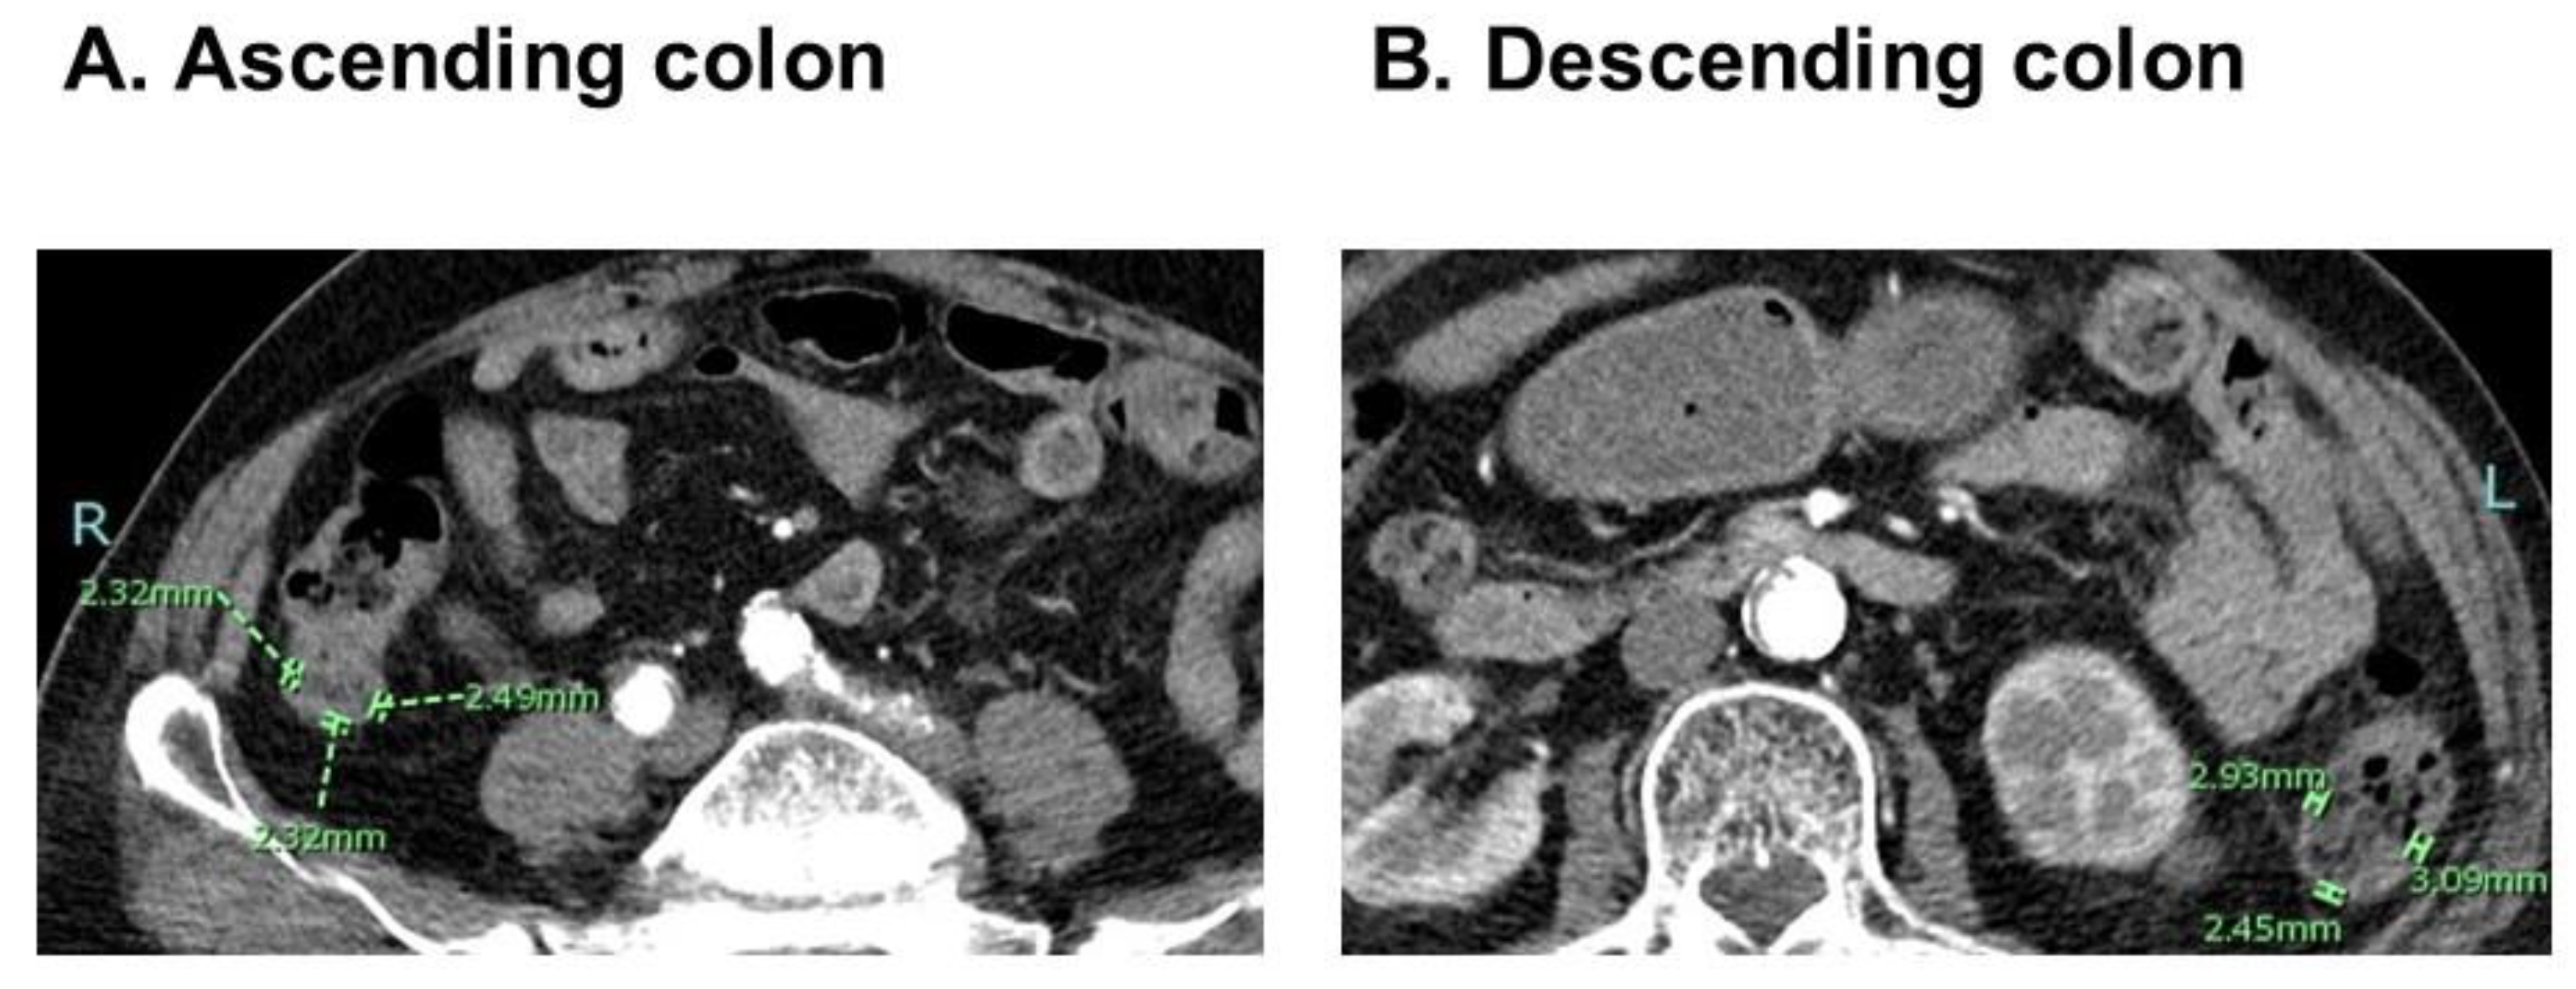

2.2. Measurement of CWT